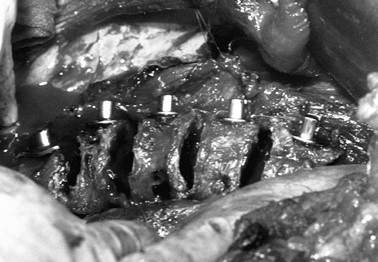

treat all thoracolumbar or lumbar structural curves greater than 65° by

balanced spine, and it enhances the fusion rate (Fig. 155.2).

Figure 155.2. A: A 26-year-old woman with an increasing throracolumbar curve and low back pain. B: A lateral x-ray reveals a junctional kyphosis from T11 to L1. C:

The postoperative AP x-ray shows correction of the curve to 20° with titanium cages filled with autogenous bone placed between T11 and L3. D: The lateral x-ray demonstrates the restoration of the normal lordosis between T11 and L3. |

either the thoracolumbar or the lumbar area, an anterior approach using

kyphosis of the thoracolumbar or lumbar spine, we have used titanium

cages to correct sagittal alignment. The cage size is selected to

restore each disc space to a more lordotic posture.